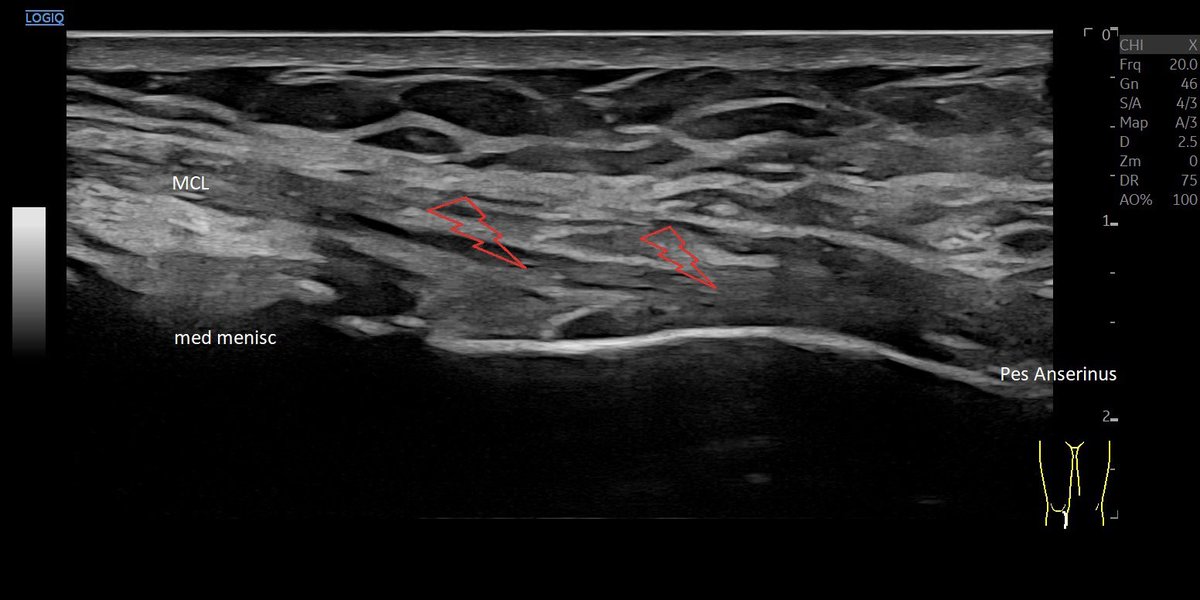

drtomaspascual@drtomaspascual·

🦵🏼 Chronic proximal partial tear of the MCL, in painful but stable knee. 💉US guided Infiltration around the Ligament. Easy and Secure, with excellent results.

JP Munoz • MSK

INSIDE OUT SUTURE medial meniscus repair: Normal ultrasound assessment